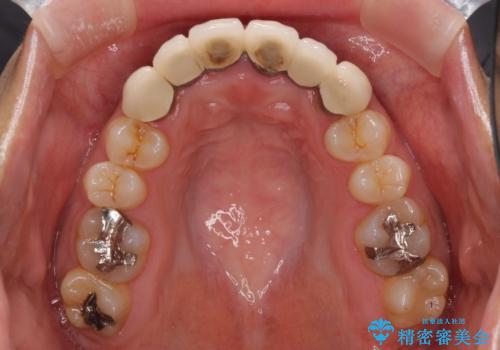

- 審美的ではない上の前歯とデコボコの下の前歯、歯茎が腫れている奥歯を気にして来院された患者様です。

根管治療の必要な歯がいくつかあるため、まずは根管治療を行い、その後インビザラインにて矯正治療を行うこととしました。

矯正治療後に前歯をセラミックブリッジに、奥の銀歯はセラミックインレーやPGAインレー(ゴールドインレー)にて補綴・修復治療を行うこととしました。

矯正治療により下顎前歯を整列させたため、上顎前歯のセラミックブリッジを補綴することで口元を少し下げることができました。